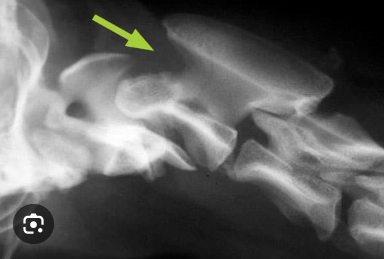

Q

whats up in them images

A

In image, the C2 arch overlaps a bit too tightly. In the right image, a fracture of C1 is visible.